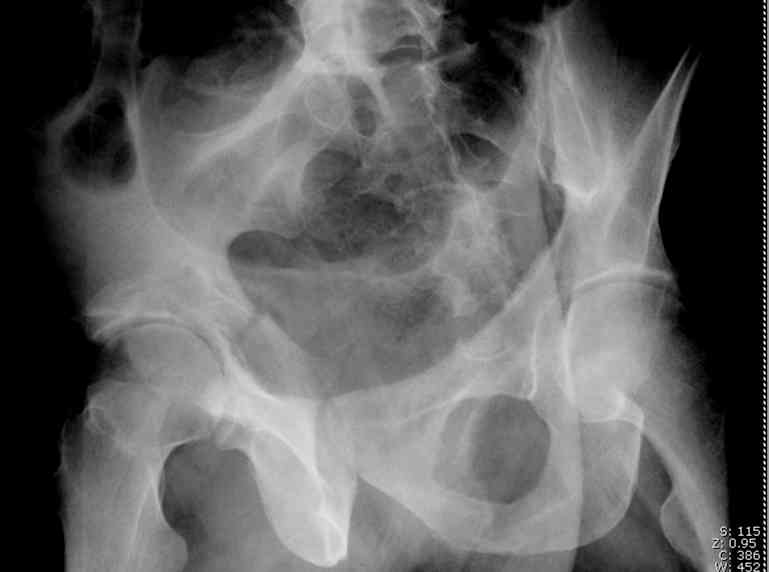

Stabilize anterior column with fluoroscopically guided screw across this end of the transverse fx - As usual, after your reduction of the femoral head, the transverse fx became minimally displaced - slightly gapped without stepoff. I usually (reduce &) stabilize the medial side of the posterior column (transverse fx) with a short plate - before placing the anterior screw unless the transverse fx is undisplaced.

Biggest problem appears to be impaction & comminution of the posterior wall fx site - you've left out some CT cuts. This is not just fragments in joint. It may leave a deficient area, &/or block satisfactory posterior wall reduction.

May need to bone graft elevated articular fragments. Lag screws & more lateral contoured plate to buttress PW. Make sure this reduction is

anatomical.